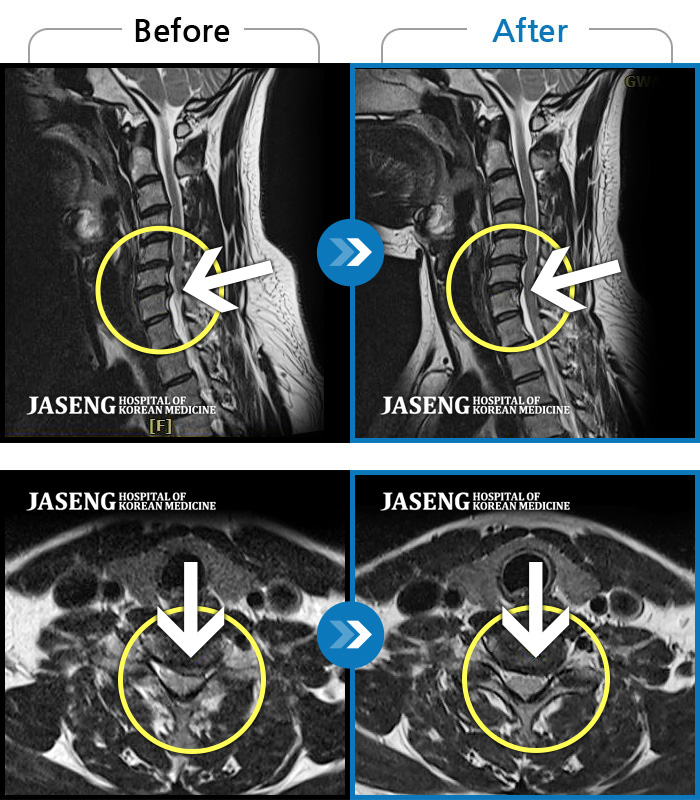

자생 비수술 한방통합치료 후

터진디스크가 흡수된 모습

비수술 치료만으로

터진 디스크 흡수

Before

After

목부터 좌측 어깨까지 통증이 심해요

2022.07.04 ~ 2024.09.02

처음 내원시 목에서 등으로 이어지는 통증 및 우측 팔 저림 증상이 심했고, 약간의 근력저하도 동반되어 일상생활이 어려운 상태였습니다.

2024.04.06 ~ 2024.11.16